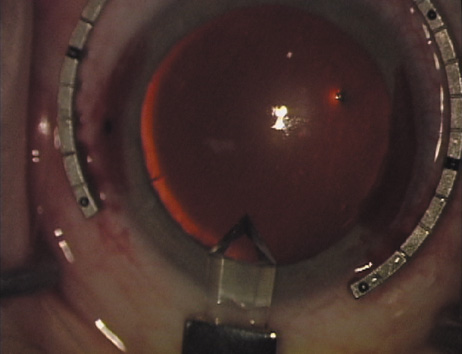

Case 1 is a 68-year-old male who presented for right cataract surgery. His refraction was −1.00 +2.25 × 80 and was recorded as reliable, consistent with his modest cataract density. Keratometry readings were 44.75 × 75 and 43.00 × 165. Corneal topography confirmed slightly more than 2.00 D of regular and slightly oblique cylinder. Consulting the nomogram, a plan was devised for a pair of LRIs to be centered over the 75-degree axis, with each incision delineating 45 degrees of arc. A single plane phaco incision was used and maintained at a size of less than 3.2 mm (Figs. 811).

Fig. 8. Steep meridian is confirmed intraoperatively by keratoscopy. In this left eye viewed from the temporal side, the “short axis” of the corneal mire is seen to be at the 75-degree meridian. (Reprinted from Hardten DR, Lindstrom RL, Davis EA. Phakic Intraocular Lenses: Principles and Practice. Thorofare, NJ: SLACK Incorporated, 2004, with permission.)